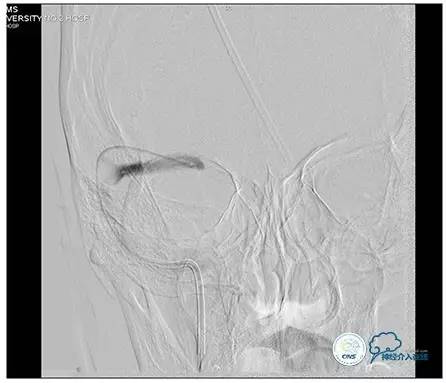

术后右侧ICA造影

术后远、近端压力差为:0

术后右侧ICA斜位

结果

术后即刻患者诉头痛完全缓解。

双眼视力较前有改善。

3天后腰穿:颅内压:75mmH2O,转当地医院眼科继续治疗。